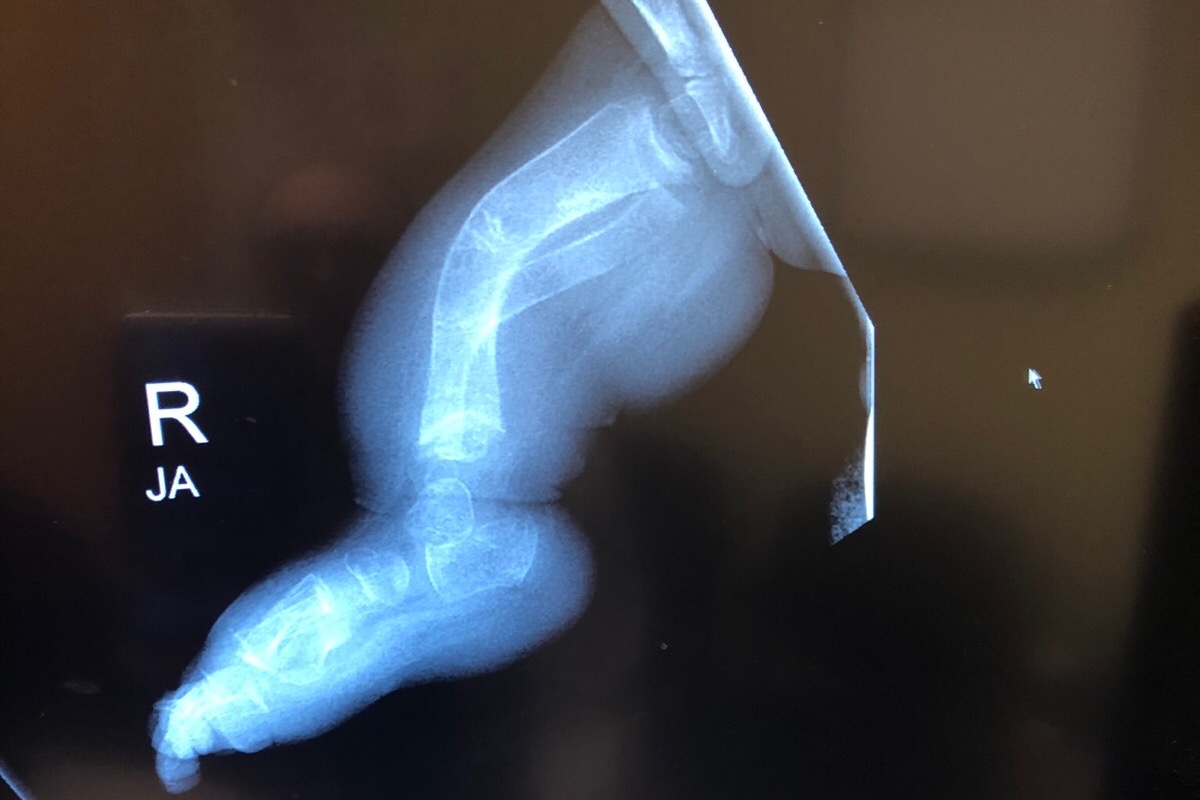

My name is Paola and im Juliet’s mom. Juliet was born September 20,2016. During my pregnancy Juliet’s bones were measuring shorter and they were bowed. The day she was born they immediately rushed her to the NICU due to her not breathing. Later on that day a NICU nurse came to talk to my husband and I and let us know that Juliet had 67 broken bones and they were all in different healing stages and they did not have a reason as to why but if they knew something they would let us know. My husband and I weren’t allowed to hold Juliet until she was about a week old due to her broken bones and not wanting us to cause more. After Juliet being in the NICU for 3 weeks they asked us if we knew what Osteogenesis Imperfecta was and I didn’t even know how to say it so at that point the Dr. told us that she suspected that, that was Juliet’s condition. She contacted a Dr. that specializes in OI and a week later they diagnosed her with type 2 and they let us know that she had already made it 3 weeks and that we don’t know how much longer she was going to live so it was best to take her home to pass away. After 7 weeks we received her genetics report and it turns out she has OI type 8. It’s a really rare type that was just discovered not too long ago. As of today we go along with what Juliet’s body tells us. She will be 3 this year and she has had over 200 fractures in her body. The dr recently decided that Juliet is ready for rodding surgery. First we will start with femurs then we will do Tibias. Hopefully one day Juliet will walk. As you all know anything that involves drs is a lot of money and as much and Juliet’s dad and i want to cover all the expenses it is impossible. The money raised will go towards Juliet’s surgery and wheelchair. We would really appreciate the help and thank you so much ❤️